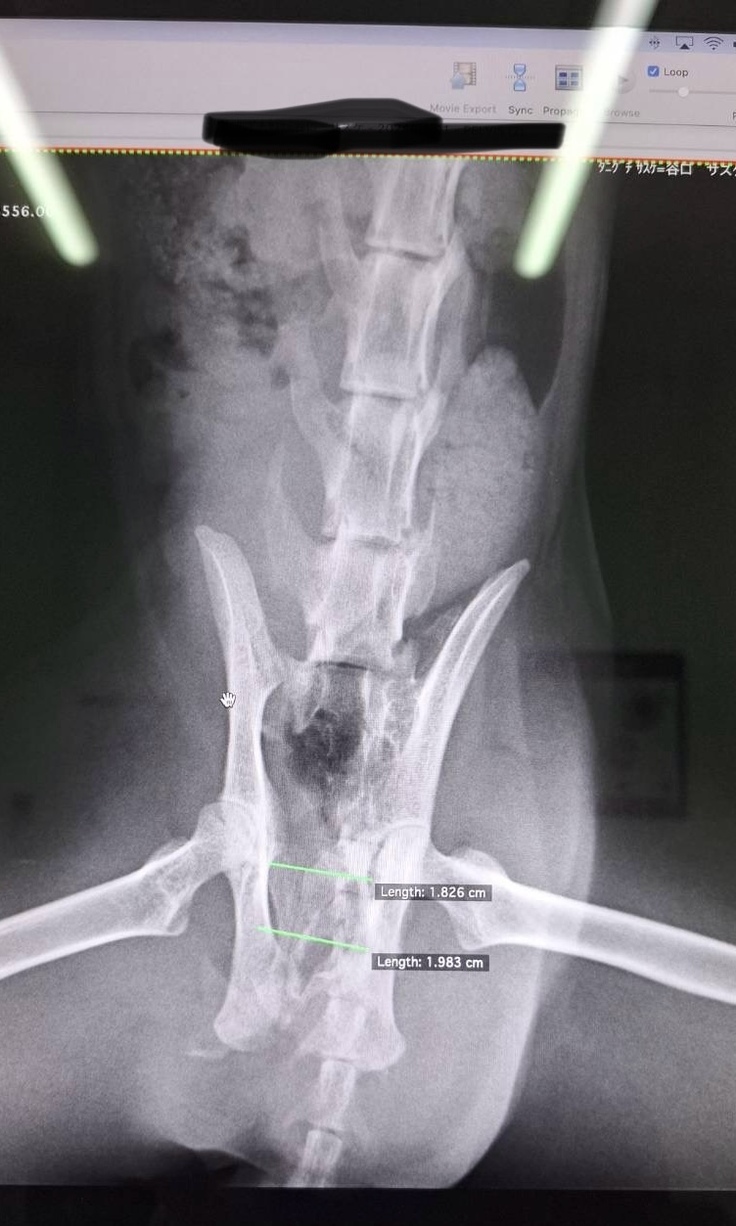

レントゲン結果内臓は問題ないけれど、

骨盤骨折です😢

これから病院通い必要になります😢